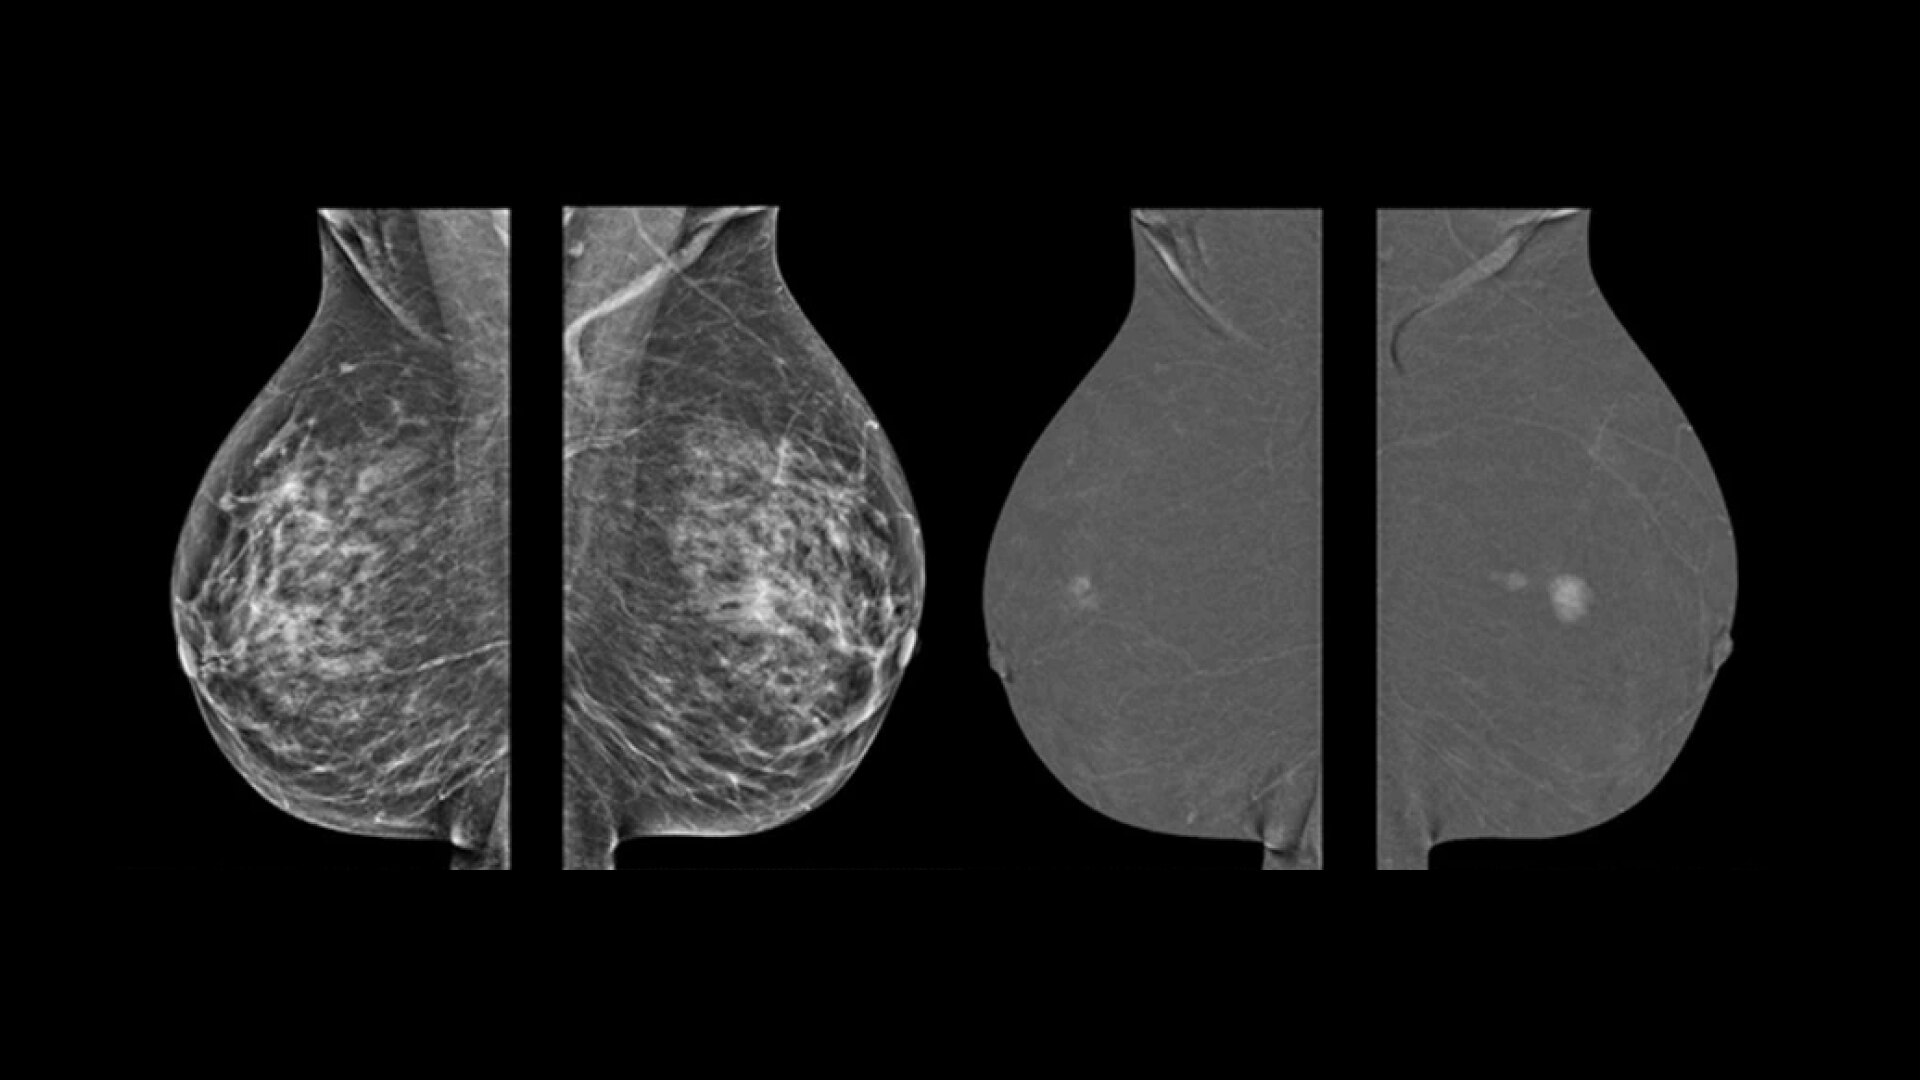

Раскройте возможности спектральной визуализации с продвинутыми 3D возможностями